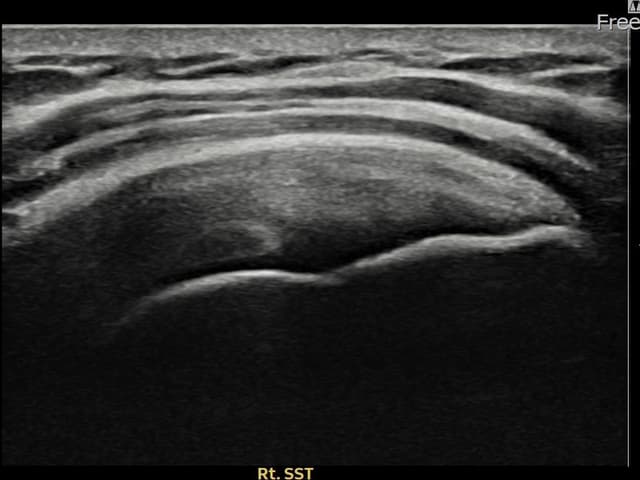

[촬영시기:23.12.14~24.02.22]

[어깨인대 축소봉합술] 우측 어깨 후방 통증과 외회전 시 심한 통증으로 내원하셨습니다.